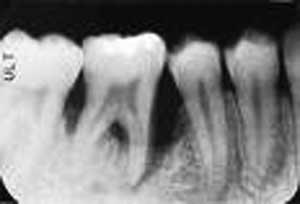

halo emel, kasus anda sepertinya masalah penyakit periodontal, penyakit yang menyerang jaringan penyangga gigi, salah satu jalan memang harus dilakukan tindakan scaling atau pembersihan karang gigi secara seksama,

karena karang gigi tidak hanya dilapisan luar gusi tetapi terdapat juga didalam gusi ( sub gingiva )